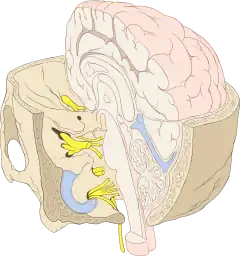

Cranial nerves as they pass through the skull base to the brain | |

After emerging from the brain, the cranial nerves travel within the skull, and some must leave it in order to reach their destinations. Often the nerves pass through holes in the skull, called foramina, as they travel to their destinations. Other nerves pass through bony canals, longer pathways enclosed by bone. These foramina and canals may contain more than one cranial nerve and may also contain blood vessels.[13]

- The oculomotor nerve (III), trochlear nerve (IV), abducens nerve (VI) and the ophthalmic branch of the trigeminal nerve (V1) travel through the cavernous sinus into the superior orbital fissure, passing out of the skull into the orbit.

- The maxillary division of the trigeminal nerve (V2) passes through foramen rotundum in the sphenoid bone.

- The mandibular division of the trigeminal nerve (V3) passes through foramen ovale of the sphenoid bone.

- The facial nerve (VII) and vestibulocochlear nerve (VIII) both enter the internal auditory canal in the temporal bone. The facial nerve then reaches the side of the face by using the stylomastoid foramen, also in the temporal bone. Its fibers then spread out to reach and control all of the muscles of facial expression. The vestibulocochlear nerve reaches the organs that control balance and hearing in the temporal bone and therefore does not reach the external surface of the skull.

- The glossopharyngeal (IX), vagus (X) and accessory nerve (XI) all leave the skull via the jugular foramen to enter the neck. The glossopharyngeal nerve provides sensation to the upper throat and the back of the tongue, the vagus supplies the muscles in the larynx and continues downward to supply parasympathetic supply to the chest and abdomen. The accessory nerve controls the trapezius and sternocleidomastoid muscles in the neck and shoulder.

- The hypoglossal nerve (XII) exits the skull using the hypoglossal canal in the occipital bone.